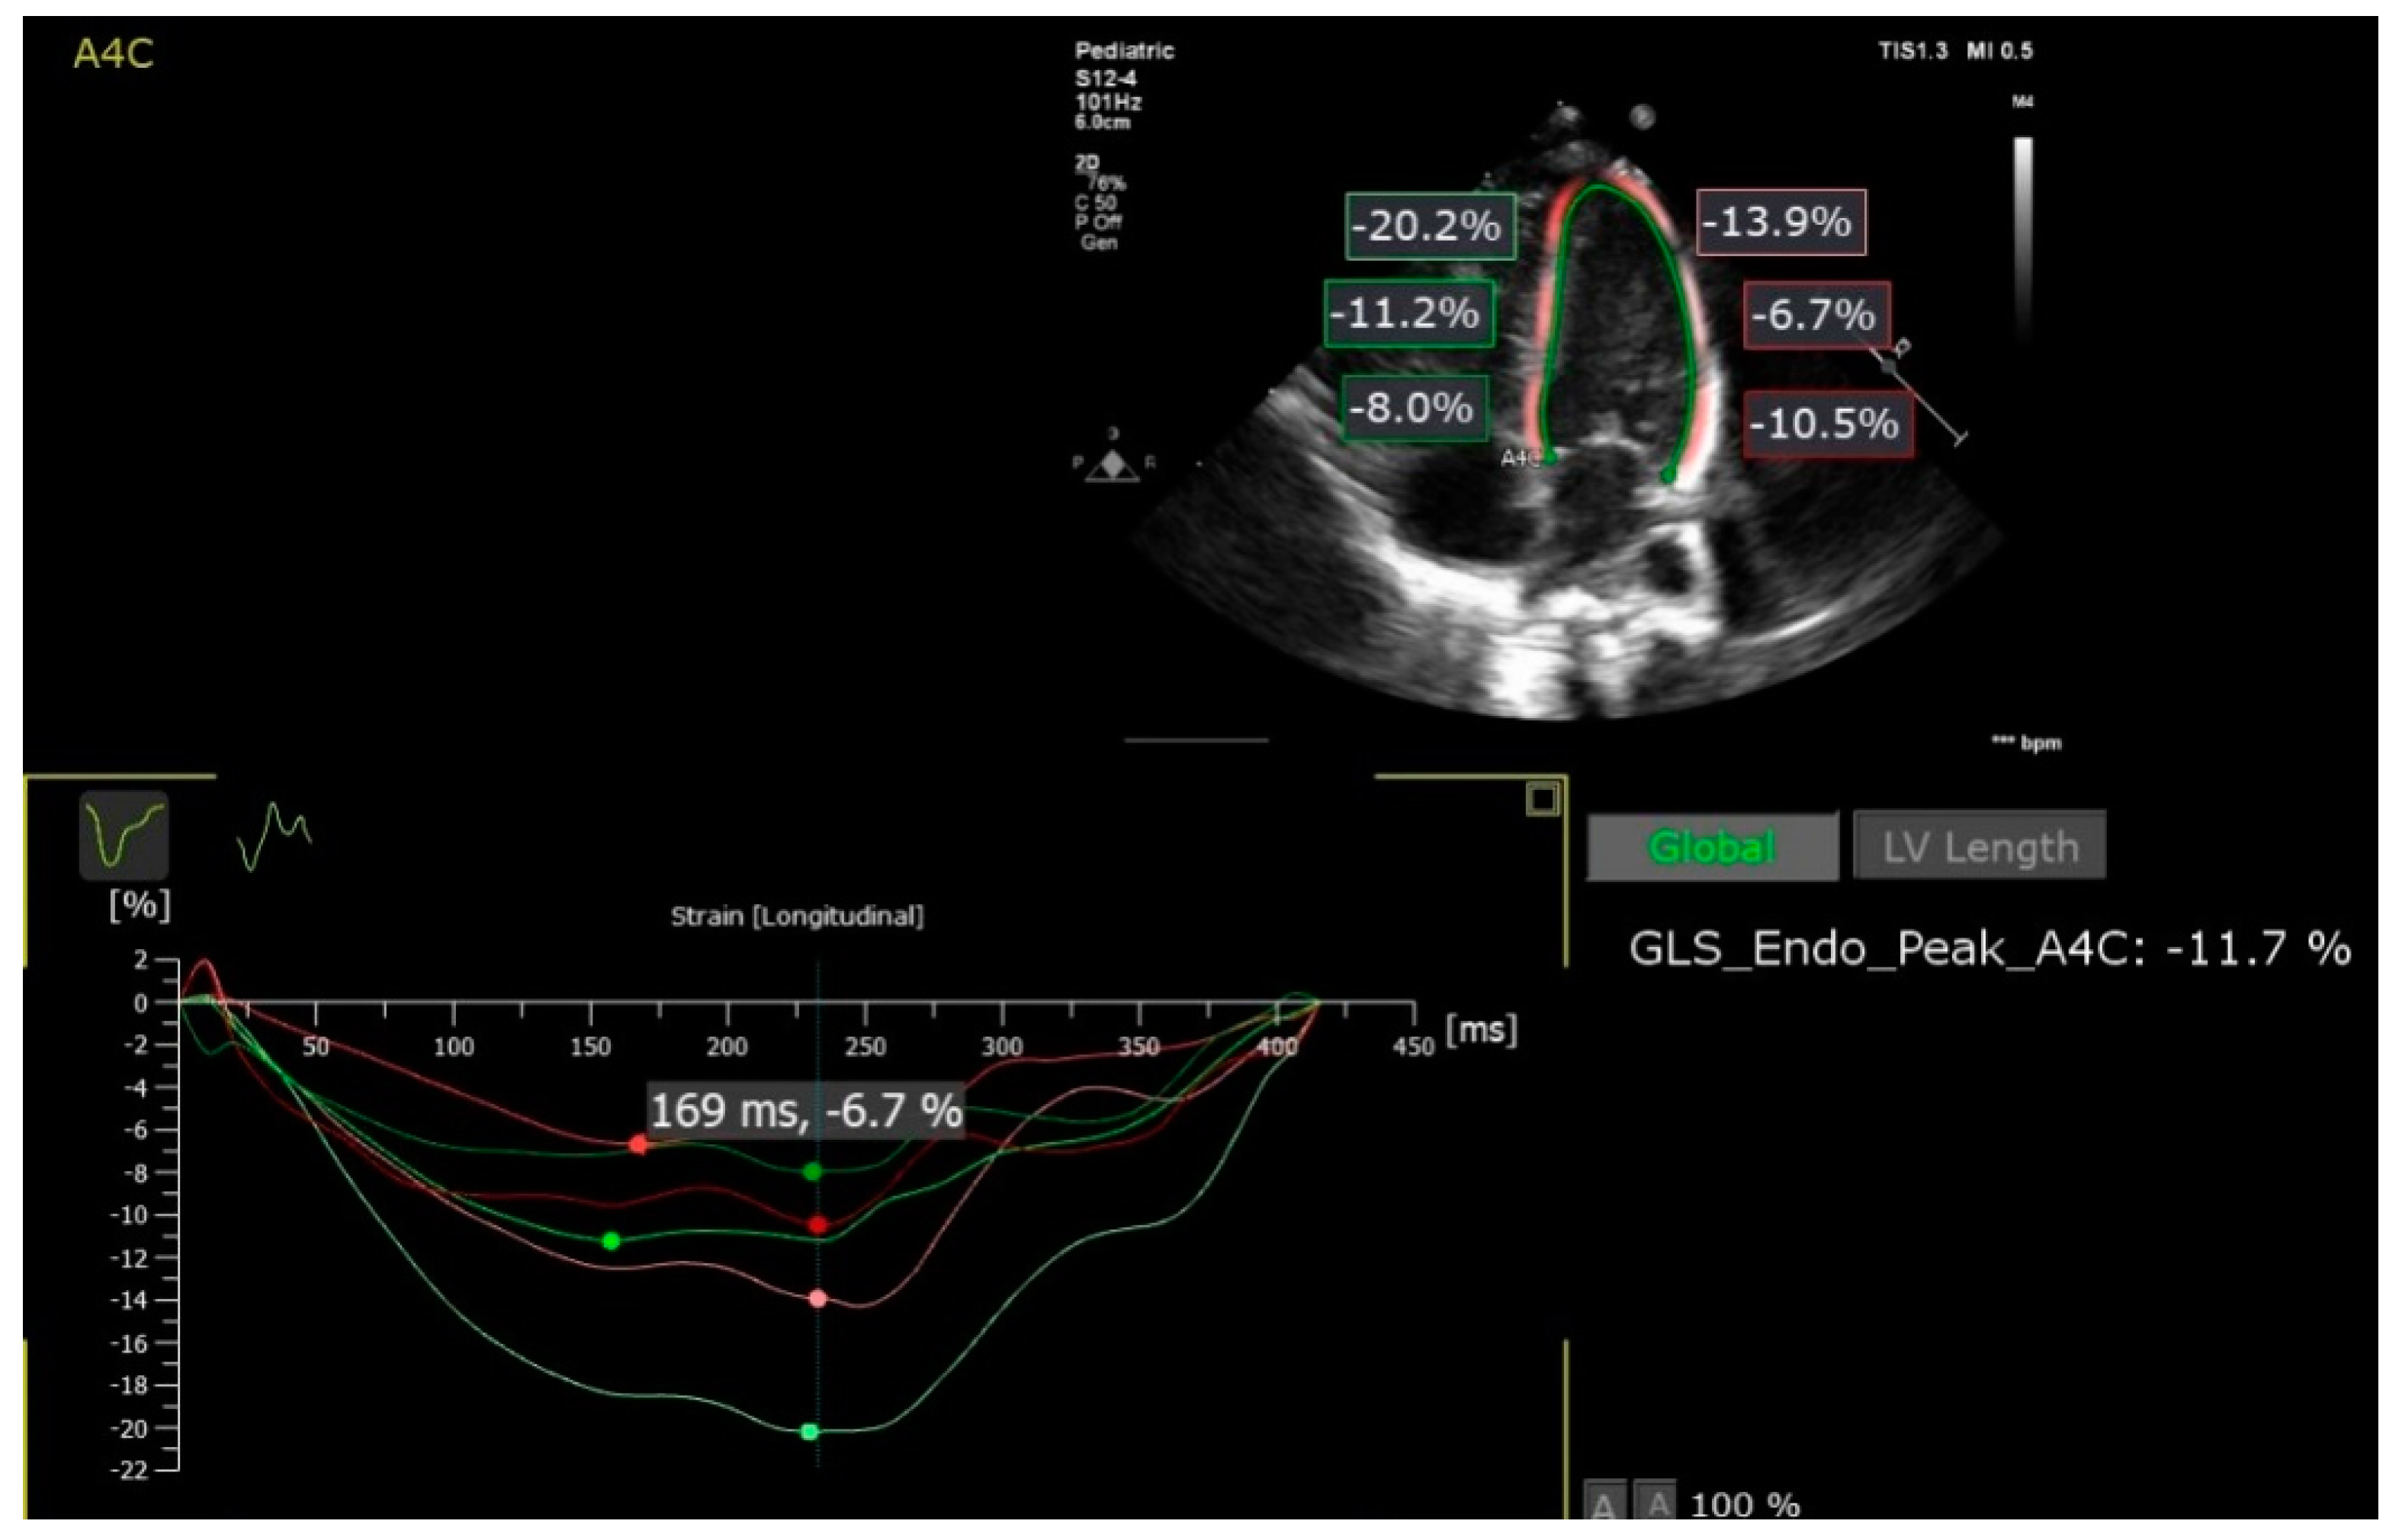

2.1. Speckle-Tracking Analysis

| Left ventricle lateral wall basal | LV Basal | Strain measured on the basal portion of the left ventricle lateral wall |

| Left ventricle lateral wall medial | LV Medial | Strain measured on the medial portion of the left ventricle lateral wall |

| Left ventricle lateral wall apical | LV Apical | Strain measured on the apical portion of the left ventricle lateral wall |

| Inter-ventricular septum basal | Inter V Basal | Strain measured on the basal portion of the inter-ventricular septum |

| Inter-ventricular septum medial | Inter V Medial | Strain measured on the medial portion of the inter-ventricular septum |

| Inter-ventricular septum apical | Inter V Apical | Strain measured on the apical portion of the inter-ventricular septum |

| Left ventricle peak global strain | LV pGLS | Peak Global longitudinal strain of the left ventricle |